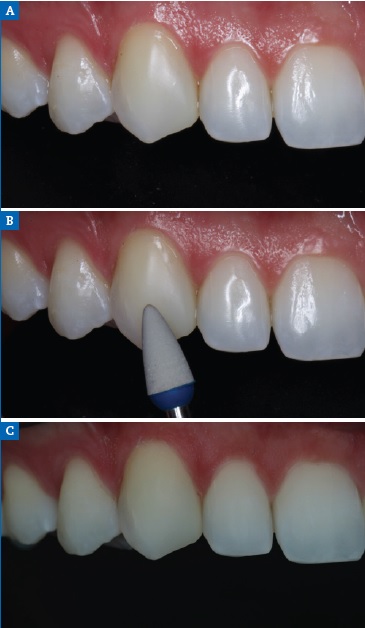

Then, to improve the morphology of the microdontic lateral incisors, a nanohybrid ORMOCER-based composite was applied. The right and left maxillary canines were also restored on the mesial face to enhance their anatomical shape (Figure 20A). This treatment plan made it possible to improve the Bolton discrepancy in the anterior mandibular excess relationship from a value of 83.1% to 79.6%. Diamond impregnated silicone polishers were used after occlusal adjustment (Figure 20B).

Cross-polarized photography revealed the monoshade resin color integration with natural teeth (Figure 20C). Intraorally, an optimal overbite and an overjet relationship were established, as was a good buccal occlusion with a Class I molar and canine. The gingival recession on the left mandibular central incisor was also improved. At the 3-year follow-up, the rehabilitation showed good soft-tissue adaptation and excellent esthetic maintenance (Figures 21).

Figure 20 Case 3 lateral view: (A) Postoperative view, (B) Final polishing, (C) Photography with cross-polarization.